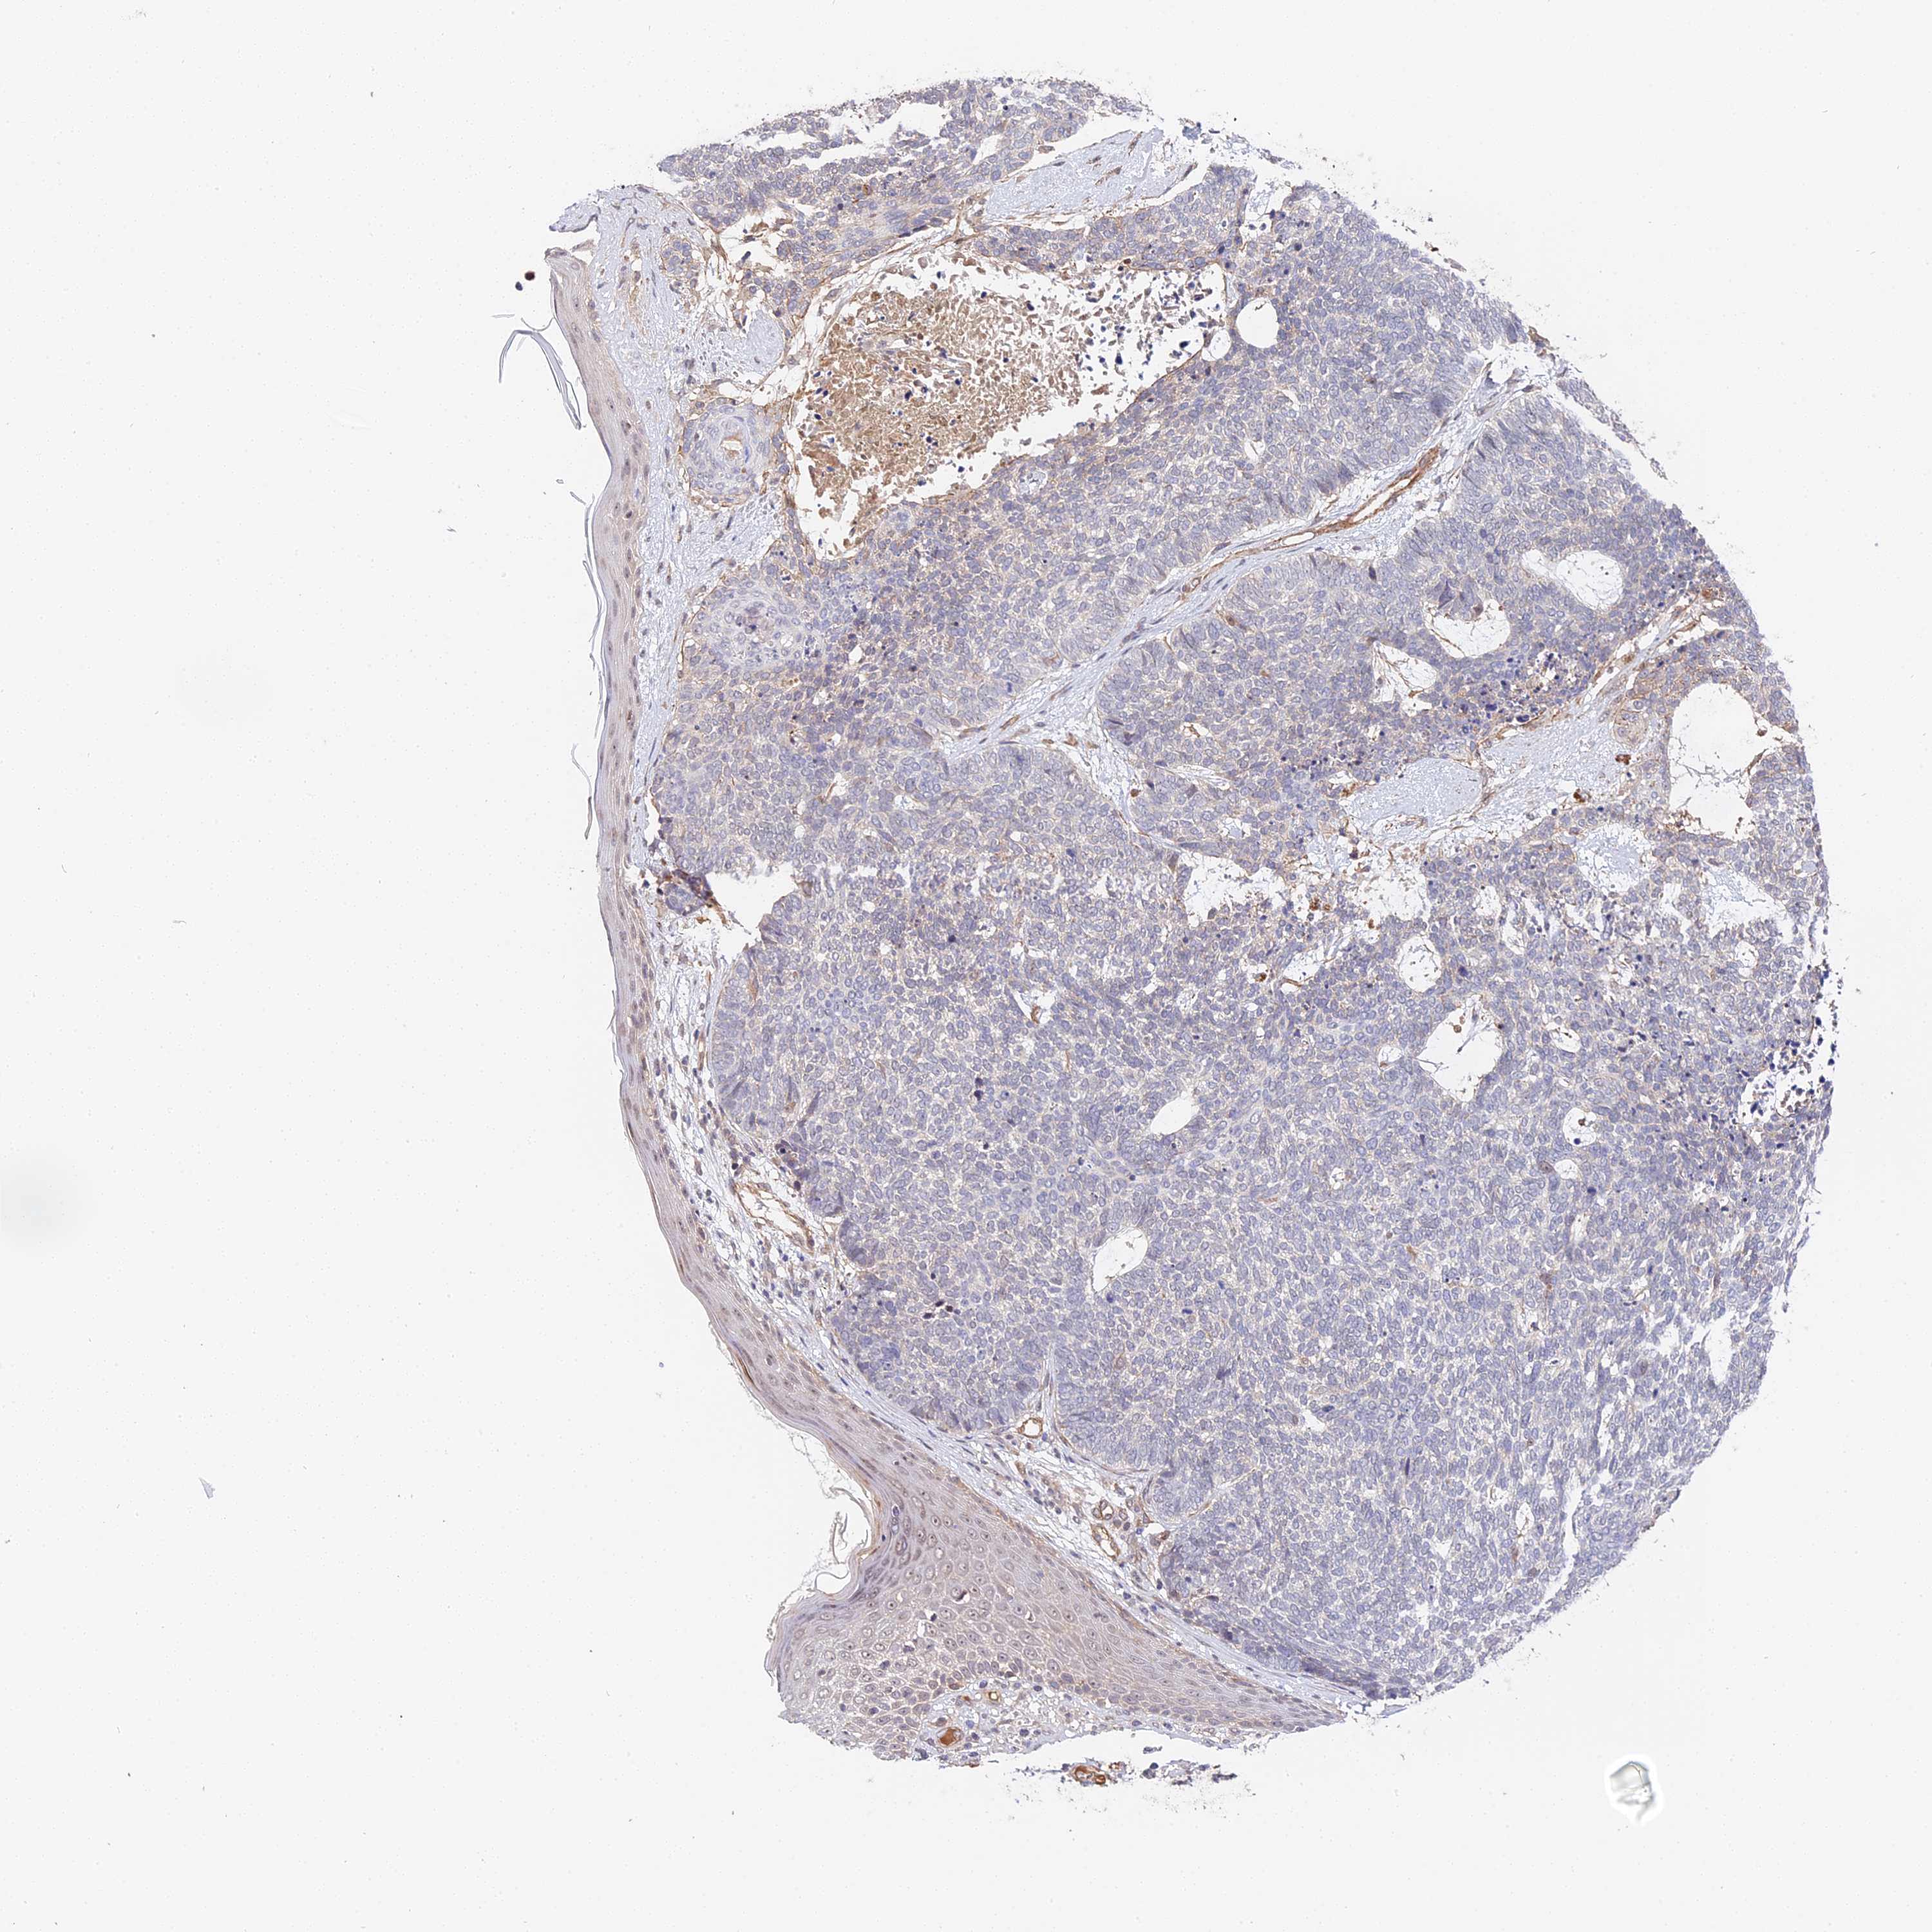

SKIN CANCER - Protein expressioni

A mouse-over function shows sample information and annotation data. Click on an image to view it in a full screen mode. Samples can be filtered based on level of antibody staining by selecting one or several of the following categories: high, medium, low and not detected. The assay and annotation is described here.

Antibody stainingi

Antibody staining in the annotated cell types in the current human tissue is reported as not detected, low, medium, or high, based on conventional immunohistochemistry profiling in selected tissues. This score is based on the combination of the staining intensity and fraction of stained cells.

Each image is clickable and will lead to virtual microscopy that enables deeper exploration of all samples and also displays staining intensity scores, fraction scores and subcellular localization as well as patient and tissue information for each sample.

Antibody HPA041045

Antibody HPA041968

Squamous cell carcinoma, NOS

Basal cell carcinoma